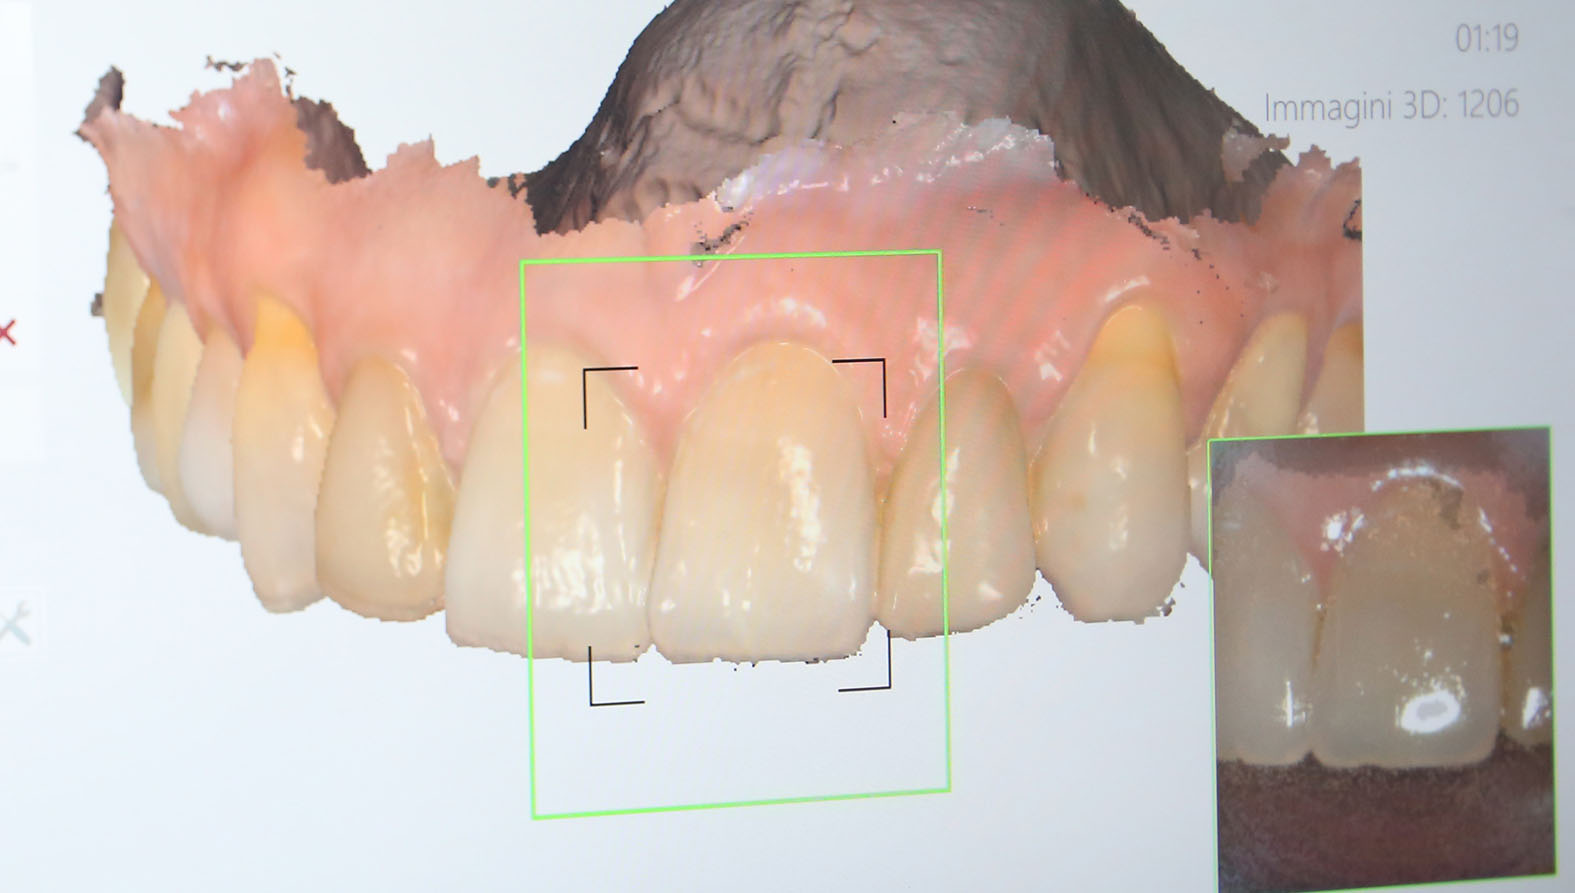

Quali sono i passaggi per arrivare ad ottenere una tale precisione? Tutto inizia dalla prima visita, dove attraverso un’ esame clinico e radiografico, si cercherà di capire se il paziente è idoneo ad una chirurgia implantare. Successivamnete inizierà la seconda fase, la più delicata, dove saranno rilevate le impronte digitali, verrà eseguita una tac volumetrica, e successivamente verranno scattate le fotografie intra ed extraorali. Nel caso del paz edentulo verrà ribasata la sua attuale protesi e scansionata, in maniera tale da poter creare una dima chirurgica perfetta per la tac

Successivamente inizierà la fase di progettazione, dove un programma dedicato elaborerà tutti i dati acquisiti. Inoltre verra’ coinvolto il Tecnico, che svilupperà il progetto Protesico definitivo, da sottoporre ad approvazione del paziente prima dell’intervento